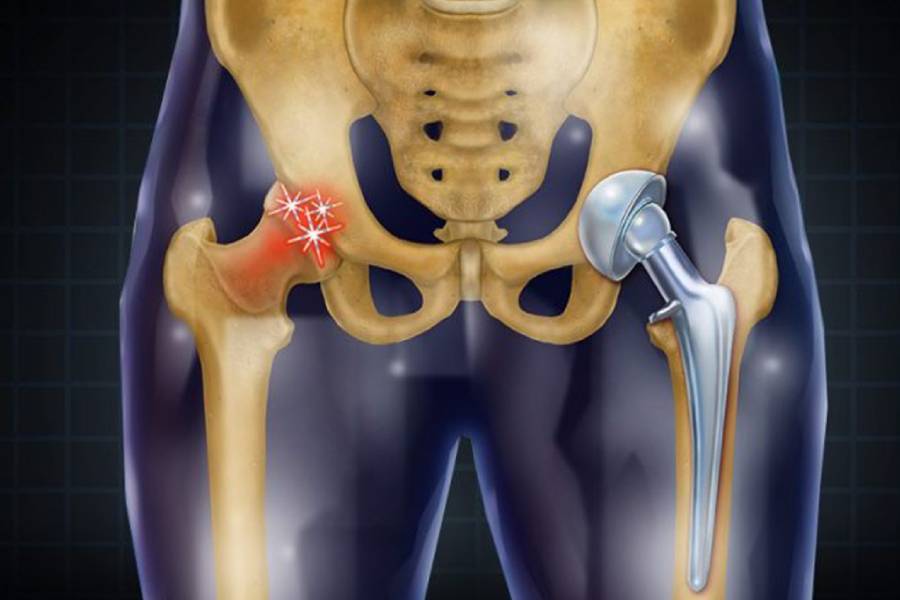

In a joint replacement hip surgery, the ball-and-socket structure of the hip joint is replaced with an artificial implant, helping patients regain pain-free movement after arthritis or hip fractures.